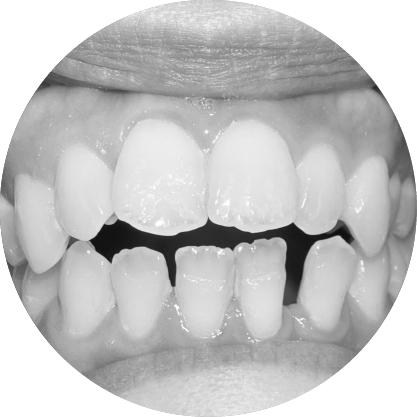

ตัวอย่างในชีวิตจริง